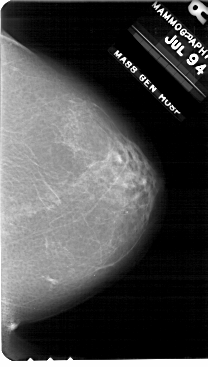

A_1707_1.RIGHT_MLO

RIGHT_MLO LINES 5491 PIXELS_PER_LINE 3721 BITS_PER_PIXEL 12 RESOLUTION 43.5 NON_OVERLAY